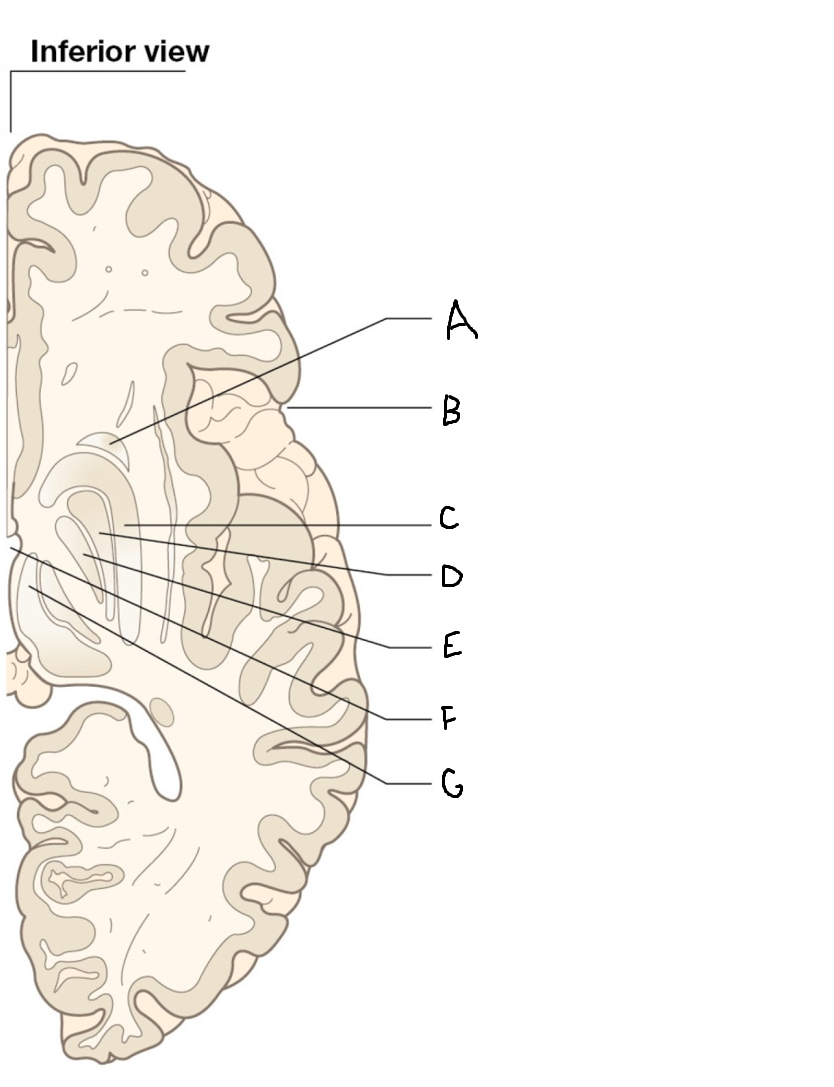

A

head of caudate nucleus

C

putamen

D

external segment of globus pallidus

E

internal segment of globus pallidus

F

third ventricle

G

thalamus